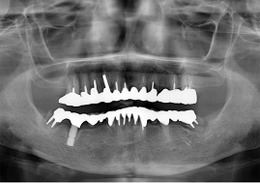

ALL-ON-4(オールオンフォー)の症例写真

上顎のALL-ON-4(ノーベルクリニシャンを使用したフラップレス術式)

- 主訴

- 歯周病で歯がグラグラするので噛めない

- 治療内容

- 上顎に残存していた歯を抜歯。歯肉の治癒後にフラップレス手術にてインプラント埋入を行い、その場で準備してあった上顎上部構造を仮歯として、ねじ固定式で装着

- 治療費用

- 上顎ALL-ON-4:4,000,000円(税別)

- 治療期間

- 6ヶ月